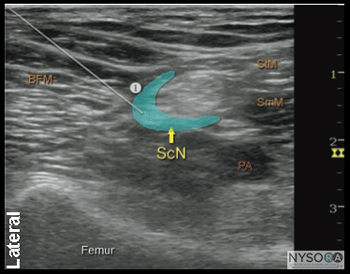

![]() Figure 7: Simulated needle path and the proper needle tip placement to block the sciatic nerve (ScN) through the lateral approach. BFM - Biceps femoris muscle, SmM - Semimembranosus muscle. StM - Semitendinosus muscle, PA- Popliteal artery. Technique With the patient in the proper position, the skin is disinfected and the transducer positioned to identify the sciatic nerve (Figure 5). If the nerve is not immediately apparent, tilting the transducer proximally or distally can help improve the contrast and bring the nerve "out" of the background (Figure 6). Alternatively, sliding the transducer slightly proximally or distally may improve the quality of the image and allow for better visualization. Once identified, a skin wheal is made on the lateral aspect of the thigh 2 to 3 cm above the lateral edge of the transducer. Then the needle is inserted in-plane in a horizontal orientation from the lateral aspect of the thigh and advanced toward the sciatic nerve (Figure 7). If nerve stimulation is used (0.5 mA, 0.1 msec), the contact of the needle tip with the sciatic nerve usually is associated with a motor response of the calf or foot. Once the needle tip is witnessed adjacent to the nerve, and after careful aspiration, 1 to 2 mL of local anesthetic is injected to confirm the proper injection site. Such injection should result in distribution of the local anesthetic within the epineural sheath, and often, separation of the TN and CPN. When injection of the local anesthetic does not appear to result in a spread around the sciatic nerve (Figure 8), additional needle repositions and injections may be necessary. When injecting into the epineurium, correct injection is recognized as local anesthetic spread proximally and distally to the site of the injection around both divisions of the nerve. This typically results in separation of TN and CPN during and after the injection.